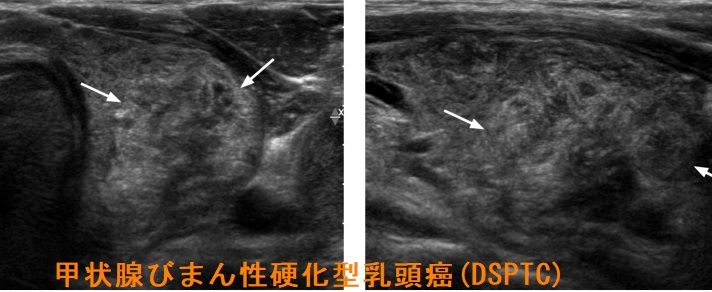

- 甲状腺超音波(エコー)検査において、不均一な病変で

等エコー(48.4%)、びまん性粒状石灰化(52.3%)、血流は乏しい(71.6%)

- 甲状腺エコーで、境界不明瞭で不均質な病変;等エコー(48.4%)、びまん性粒状石灰化(52.3%)、血流は乏しい(71.6%)[Clin Radiol. 2022 May;77(5):e356-e362.]

(エコー画像;Ultrasonography. 2017 Apr 36(2) 103–110.)